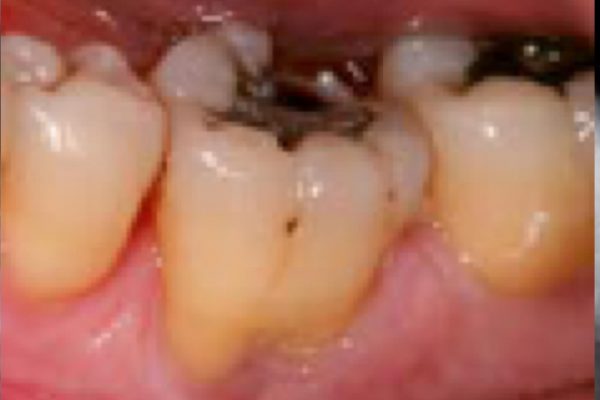

A 55-year-old patient presented with significant mobility in tooth LL6.

A retro-alveolar radiographic examination showed a level three furcation defect preventing the preservation of the tooth.

The decision was to extract the tooth and perform bone filling so as to permit implant placement.